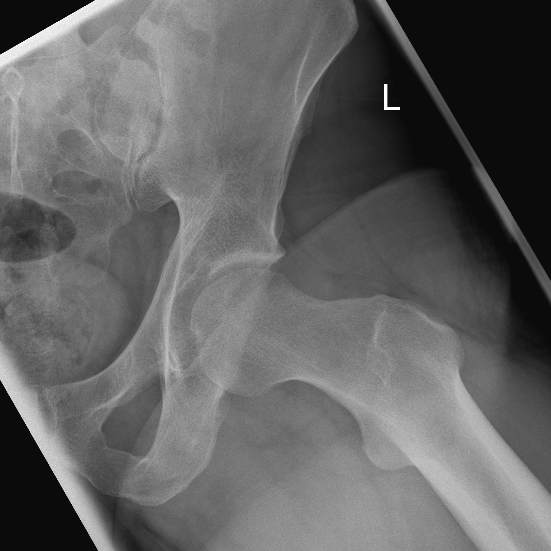

Ein stark vorstehender knöcherner Pfannenrand (Pincer- oder Beißzangen-Impingement) oder ein inhomogener knöcherner Übergang des Hüftkopfes in den Schenkelhals (sog. CAM- oder Nockenwellen-Impingement) liegt oft bei Hüfterkrankungen vor, die schon im Kindesalter beginnen. Allerdings treten die ersten Beschwerden häufig erst im Erwachsenenalter auf. Die Hüftarthroskopie bietet dabei die Möglichkeit einklemmende Knochenüberstände abzutragen und die Kontur des Hüftkopf-Schenkelhalsbereiches durch spezielle Fräsen wieder zu normalisieren. Dadurch wird ein vorzeitiger Hüftverschleiß verhindert.